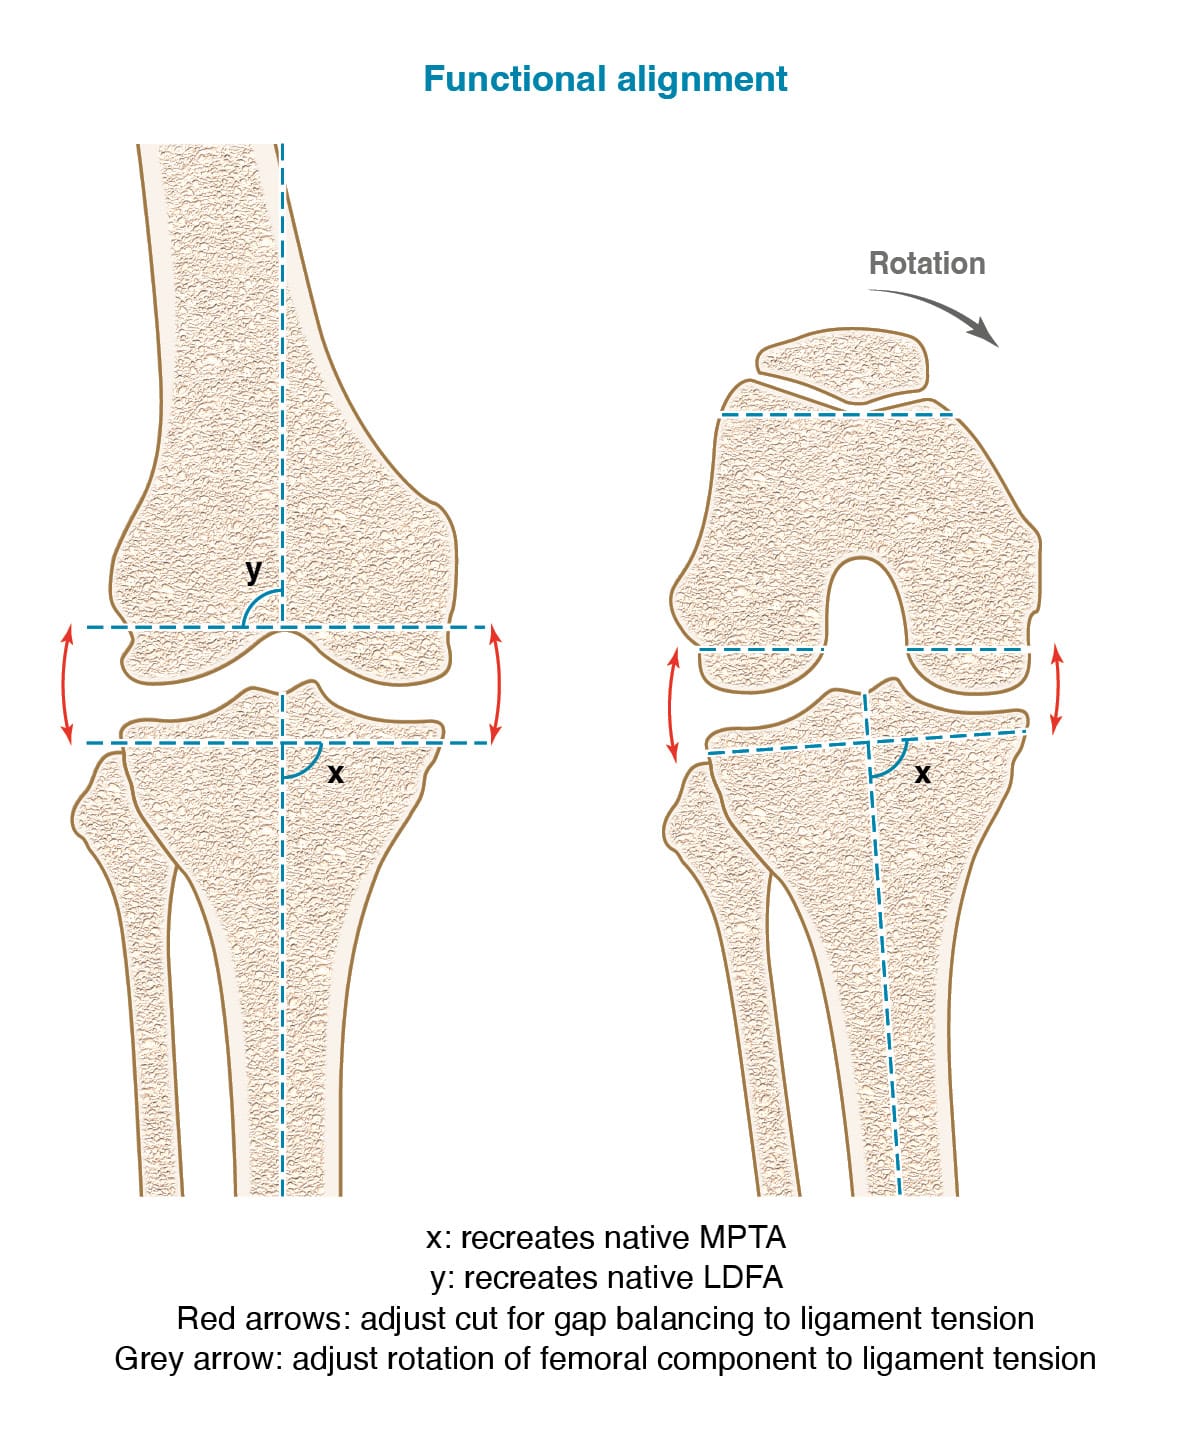

Functional Alignment is intrinsically linked to the advancement of robotic surgery. The fundamentals of the technique are based on the previous alignment philosophy mentioned before: achieving perfect gap balancing with personalized bone cuts. Robotic surgery is a key tool for this technique allowing one degree precision bone cuts. It is promoted by several authors : Sebastien Parratte [15] Parratte S, Van Overschelde P, Bandi M, Ozturk BY, Batailler C. An anatomo-functional implant positioning technique with robotic assistance for primary TKA allows the restoration of the native knee alignment and a natural functional ligament pattern, with a faster recovery at 6 months compared to an adjusted mechanical technique. Knee Surg Sports Traumatol Arthrosc Off J ESSKA 2022. https://doi.org/10.1007/s00167-022-06995-4., Sebastien Lustig[16] Lustig S, Sappey-Marinier E, Fary C, Servien E, Parratte S, Batailler C. Personalized alignment in total knee arthroplasty: current concepts. SICOT-J 2021;7:19. https://doi.org/10.1051/sicotj/2021021., Fares Haddad [17] Chang JS, Kayani B, Wallace C, Haddad FS. Functional alignment achieves soft-tissue balance in total knee arthroplasty as measured with quantitative sensor-guided technology. Bone Jt J 2021;103-B:507–14. https://doi.org/10.1302/0301-620X.103B.BJJ-2020-0940.R1..

The surgeon chooses the femoral distal angle and proximal tibial angle that he wants to recreate during the surgery. Knee laxity is measured before the bone cuts, with spacer and with the trials implants to fine-tune knee laxity. One of the key advantages of this technique is to be able to play with parameters as rotation and flexion of the femoral component for gap balancing. (Figure 9) However, this technique’s limitation lies in its reliance on the availability of robotic surgery, which is not yet widespread.